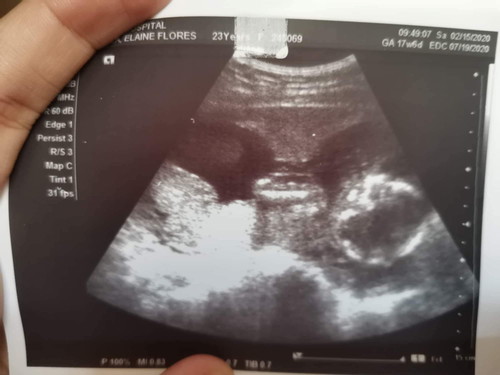

4 Months Pregnant

Nag pa-Pelvic Ultrasound po ako last Saturday and that was the first time we saw our baby ? Sa tingin nio po okay naman po ang baby ko? Like yung sa Position nia? ? Based sa Ultrasound? Thank you po.

Sakin nung 4th month ko ganito na siya.